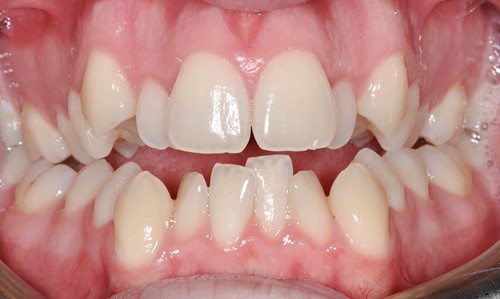

Vậy như thế nào là khớp cắn bình thường và khớp cắn lệch lạc? Đáng ngạc nhiên là không chỉ đơn thuần có một câu trả lời. Một khớp cắn bình thường được mô tả bằng những tiêu chí như: lý tưởng, phù hợp giải phẫu, mang tính trung bình, mang tính thẩm mỹ, hợp lý, đảm bảo chức năng cắn và khớp cắn không ảnh hưởng tới sức khỏe răng miệng. Do vậy, trên thực tế, cùng một vấn đề nhưng có thể có tồn tại nhiều hướng giải quyết khác nhau: điều trị hay không điều trị. Lệch lạc khớp cắn không phải là một bệnh nhưng là một biến thể khác so với tình trạng bình thường và có thể ảnh hưởng không tốt đến tình trạng sức khỏe răng miệng nói chung. Về cơ bản, có ba nguyên nhân chính dẫn tới việc cần phải tiến hành chỉnh nha: 1- Tình trạng, khấp khểnh, vẩu răng-hàm 2- Điều chỉnh chức năng ăn nhai của răng 3- Loại bỏ các nguy cơ có thể gây tổn hại tới sự khỏe mạnh lâu dài của răng và mô quanh răng.

Chức năng cắn: Những răng không được tiếp xúc tốt với răng tương ứng ở hàm đối diện có thể gây khó khăn khi ăn uống và có thể dẫn tới rối loạn chức năng khớp thái dương- hàm. Tuy nhiên, mối liên hệ giữa rối loạn chức năng khớp thái dương hàm và lệch lạc khớp cắn vẫn là một vấn đề gây tranh cãi. Những cá nhân có khớp cắn không tốt, có thể cảm thấy khó khăn và ngượng ngùng khi ăn vì họ không thể cắn được miếng thức ăn bằng răng cửa của mình. Họ chỉ có thể nhai thức ăn bằng những răng phía sau. Sức khỏe răng miệng: Vệ sinh răng miệng trở nên khó khăn hơn. răng dễ có mảng bám và cao răng hơn nếu hàm răng khấp khểnh không đều. Do vậy, bệnh nhân có thể dễ bị sâu răng và các bệnh nha chu khác như viêm lợi và viêm quanh răng hơn. Tuy nhiên, nếu có một hàm răng đều đặn mà không có ý thức và thực hành vệ sinh răng miệng tốt thì cũng không thể có tình trạng vệ sinh răng miệng tốt. Nếu chải răng không đầy đủ và không đúng cách, các bệnh nha chu sẽ tiến triển bất chấp hàm răng của họ thẳng đều đến mức nào. Trong nhiều trường hợp lệch lạc khớp cắn có thể làm tổn thương cả răng và mô mềm nếu không được điều trị. Hiển nhiên rằng răng cửa hàm trên càng chìa ra nhiều bao nhiêu thì nó lại càng dễ bị tổn thương bấy nhiêu. Khi khoảng cách theo chiều ngang giữa răng cửa hàm trên và răng cửa hàm dưới là 9mm hoặc lớn hơn, nguy cơ tổn thương răng cửa hàm trên tăng lên tới hơn 40%. Giảm độ chìa ra của răng cửa hàm trên không chỉ có lợi ích trên quan điểm thẩm mỹ mà còn hạn chế tối đa nguy cơ chấn thương và sự phức tạp về lâu về dài cho cả hàm răng. Những tình trạng khớp cắn ngược, không chỉ ảnh hưởng nhiều đến vấn đề thẩm mỹ mà còn ảnh hưởng đến chức năng cắn và gây ra tình trạng mòn răng – răng sớm, răng cửa dưới bị tiêu xương ổ răng, lợi bị co…Trong trường hợp được điều trị sớm, tổn thương mô mềm sẽ dừng lại và khi phần lợi còn lại được tái tạo thì tình trạng sẽ được cải thiện một cách tự nhiên và không để lại vấn đề gì sau này.